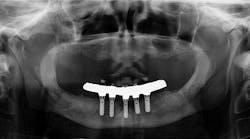

A PATIENT WHO RECENTLY MOVED TO THE AREA came in for a comprehensive exam and assessment. He had a lower fixed hybrid prosthesis put in more than five years ago that needed removal badly due to the amount of debris, plaque, and tartar that had accumulated underneath it (figure 1). Unfortunately, right away, there were two issues that challenged what normally would have been a straightforward removal:

Figure 1

- The dental office where the patient had the prosthesis placed was destroyed in a fire, and all patient records were lost. The dentist who purchased the practice had no idea who the oral surgeon was and no knowledge as to the type of implant system that had been used.

- The patient was experiencing the beginning stages of Alzheimer’s and couldn't remember anything with regard to doctors, locations, etc. Furthermore, he could not remember whether the prosthesis had ever been removed. Family members could only tell us about the patient's most recent dentist.